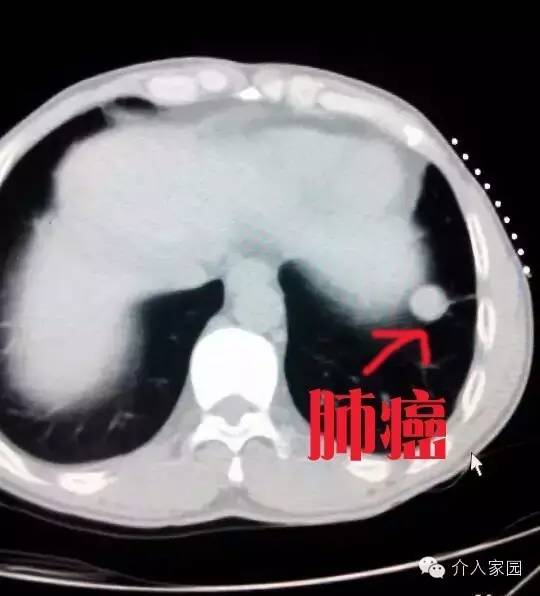

肺癌,我國最常見的腫瘤,發(fā)病率居腫瘤之首,它也會導致出血,很多病人就是因為大出血而死亡的??纯创髴c油田總醫(yī)院介入科提供的一個病例。右肺癌患者,伴咯血。如下圖,我們可以清楚地看到那一團肺癌腫塊。

這個是把腫瘤堵塞后表現(xiàn),我們可以看到,整個腫瘤消失,不再有血液營養(yǎng)供應了。所以這個患者不光止住了咯血,肺癌在失去血供營養(yǎng)后,也萎縮變小。